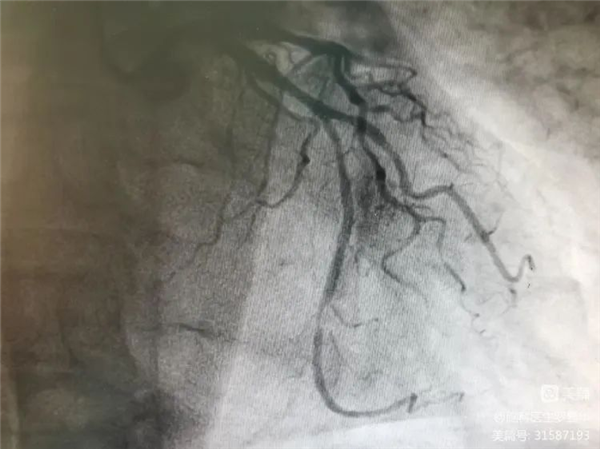

冠脉造影证实左旋支重度狭窄